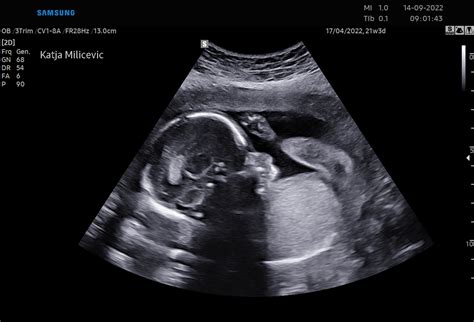

Ultrazvok v 30. Tednu Nosečnosti in Priprava na Porod

Če je vaša nosečnost brez zapletov, verjetno v tem tednu ne boste imeli ultrazvoka. Vendar pa je pri načrtovanju poroda zelo pomemben položaj posteljice. Če posteljica delno ali v celoti prekriva maternično ustje (predležeča posteljica oz. placenta previa), je to lahko razlog za zaskrbljenost in morate v tem primeru biti pripravljeni na porod s carskim rezom. Čeprav so tehnike in znanje carskega reza v zadnjih nekaj desetletjih zelo napredovale, je carski rez treba vseeno obravnavati kot izjemo. Carski rez je 40-minutna operacija, pri kateri se otrok rodi s pomočjo reza v trebušno steno oziroma maternico, kar pomeni, da ste med tem pod anestezijo. Izbrani anestetik otroku ne škoduje. Carski rez se naredi pri 1 izmed 5 žensk pri prvem porodu.

Med naslednjim pregledom bo ginekolog s pomočjo ultrazvoka določil položaj posteljice v maternici. Prav tako se ocenjuje rast ploda. Ultrazvočno naredimo standardne meritve: BIP, to je prečni presek čez glavico, HC, to je obseg glavice, AC, to je obseg trebuha in FL, to je dolžino stegnenice. Iz danih meritev ocenimo telesno težo ploda.